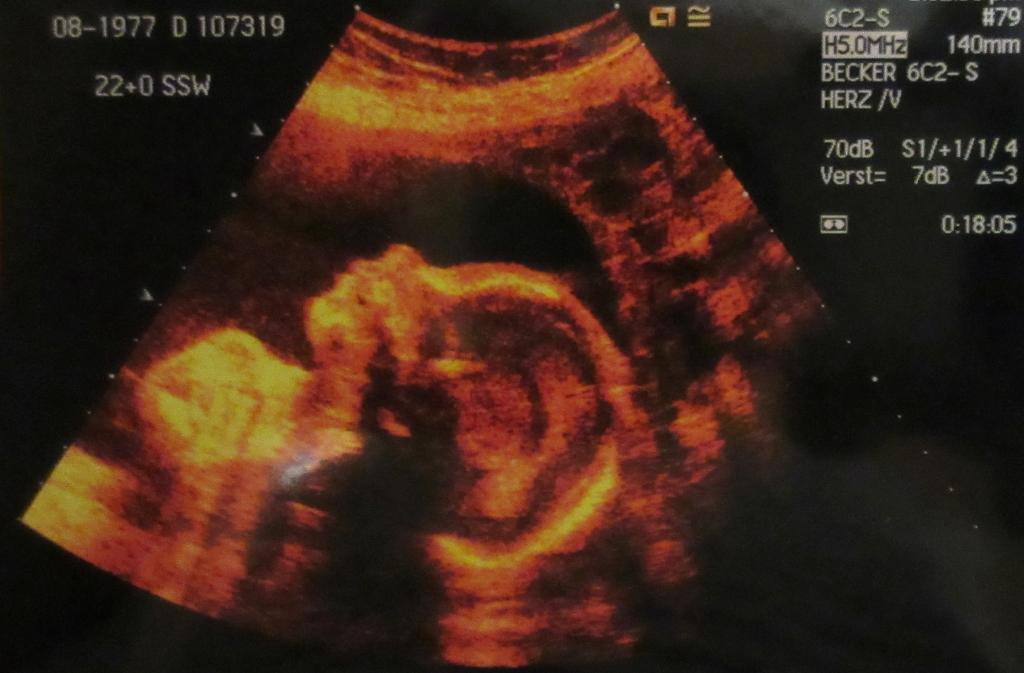

Auf diesem Foto wird ein Ultraschall durchgeführt. Das ist eine Untersuchung, mit der man das Baby im Bauch sehen kann. (Foto: dpa)

Die Eltern können die verschiedenen Stadien ihres Kindes mitverfolgen. Der Arzt macht Ultraschall-Untersuchungen. Damit bekommt man ein Bild des Babys im Bauch.

Der Kopf eines Babys auf einem Ultraschall-Bild (Foto: dpa)

„Das erste Organ, das auf dem Ultraschall-Bild zu erkennen ist, ist das Herz”, erklärt die Expertin. „Schon etwa in der sechsten Schwangerschafts-Woche beginnt es zu schlagen.” Auch Arme und Beine sind früh zu erkennen. Etwa mit 12 Wochen sind alle Organe vorhanden, auch wenn einige noch nicht ganz fertig sind.